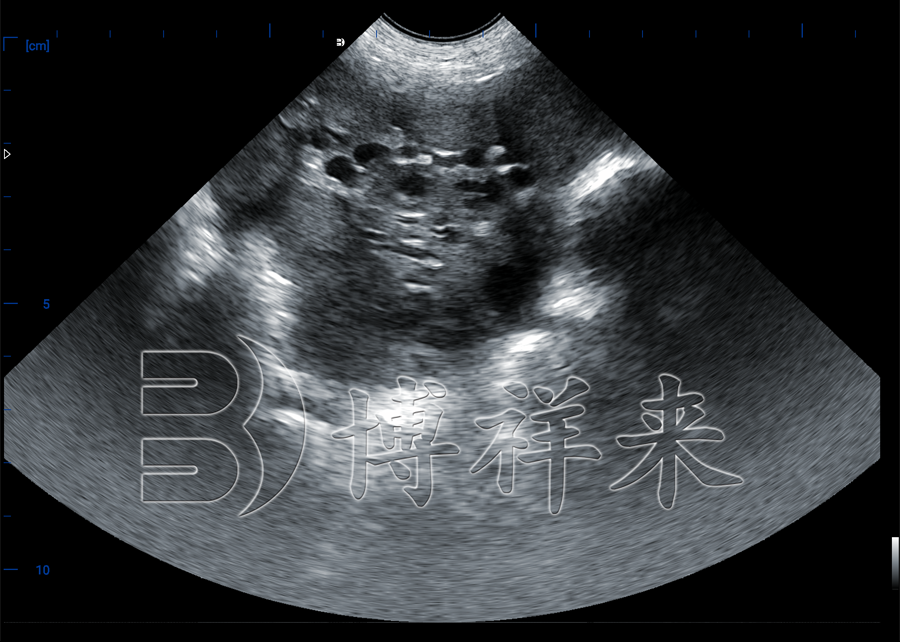

猪卵泡B超机本质上是一种针对母猪生殖结构优化的超声成像设备。

通过直肠探头靠近卵巢区域,对卵泡进行实时成像。

在B超图像中:

相比仅凭外观判断,母猪卵泡检测仪能够直接反映卵泡的真实发育状态。

博祥来在猪卵泡B超机设计中,针对母猪卵巢位置深、脂肪层变化大、个体差异明显等特点,对成像参数进行了针对性优化,使卵泡结构更容易识别。猪卵泡B超机和母猪卵泡检测仪,并不是取代经验,而是让经验更有依据。当卵巢状态可视化,配种时机就不再是“猜”。对于希望提升繁殖效率、降低返情率的猪场来说,母猪卵泡检测,已经成为越来越重要的一环。